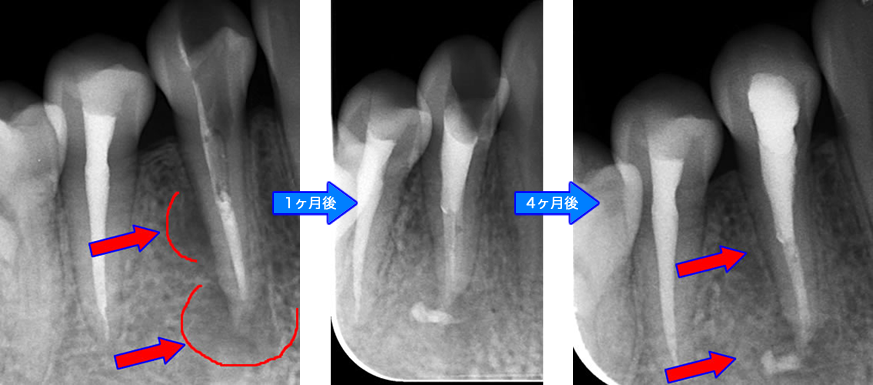

| 治療説明 | 右下第2小臼歯、他院で根管治療した後に頬側根尖部から排膿があます。X線CT画像では、根管が2本あり、そのうち舌側が根管充填されていませんでした。顕微鏡下で2根管とも根管充填処置を行い、4ヶ月で、X線透過像は消失しました。 |

| 治療説明 | クラウン・メタルコアを除去し、前医が根充した根充剤を除去、根尖まで穿通したことを確認後、根管充填を行いました。1ヶ月後には症状は消退しました。 |

|---|---|

| 治療場所 | 左側第一大臼歯 |

| 主訴 | 根尖部違和感・噛んだ時に痛む |